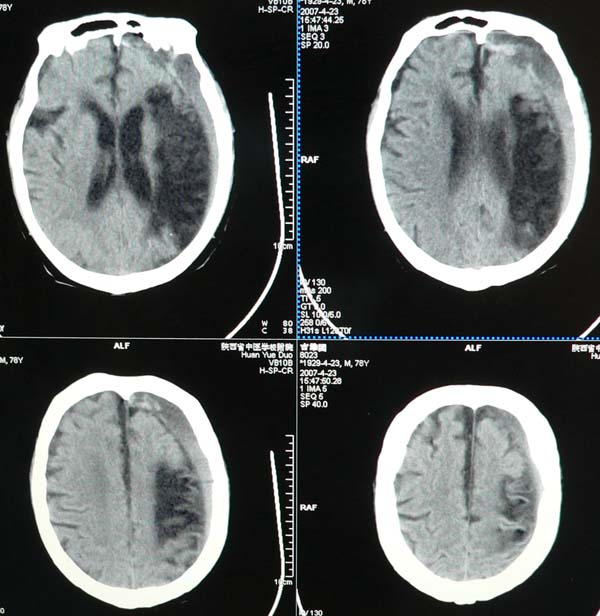

以下是引用star--868在2007-6-15 20:54:00的发言:[br]1.左侧额颞顶部亚急性硬膜下血肿并继续出血 双侧额颞顶部硬膜下积液;[br]2.左颞枕叶、左基底节区脑软化-左侧大脑中动脉栓塞;[br]双侧额颞顶部硬膜下积液应和治疗期间应用高渗脱水剂相鉴别:停用甘露醇后硬膜下积液会逐渐吸收减少,而单纯硬膜下积液无此改变和/或逐渐增多。

以下是引用狙击手在2007-6-15 21:15:00的发言:[br]软化灶就不必说了,主要是混和性血肿的渐变过程。

以下是引用老爱克斯新网客在2007-6-15 20:40:00的发言:[br]1左侧颞叶软化灶,2双侧硬膜下水瘤,3左册硬膜下血肿(多次少量出血),

以下是引用还珠格格在2007-6-16 7:07:00的发言:[br]支持.左侧额颞顶部亚急性硬膜下血肿并继续出血 双侧额颞顶部硬膜下积液;[br]2.左颞枕叶、左基底节区脑软化-左侧大脑中动脉栓塞;